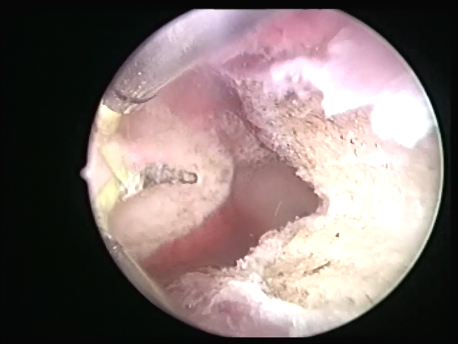

- Intrauterine foreign bodies: Missing copper T embedded in the uterine wall or retained fetal bones or pregnancy following a miscarriage can contribute to irregular bleeding, infection or subfertility.